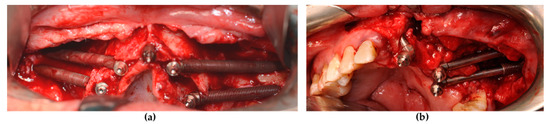

A maxillofacial type navigation system involving the use of an extraoral reference tool (onto the cranial bone) was employed in three oncologic patients in whom the residual maxillary bone was not sufficient for the fixing of the intraoral reference tool. After a final evaluation carried out by a depth gauge, zygomatic implants (Southern Implants, Irene, South Africa) were positioned via the use of implant motor or manually using a fixture mount. Standard zygomatic implants were placed in patients from the atrophic group and in oncologic patients when the implant collar was surrounded by the residual crestal bone (Figure 2a). The oncologic type of zygomatic implant was placed when there was only soft tissue around the implant collar (Figure 2b).

Figure 2. The zygomatic implant was placed and the conical abutment was screwed before suturing. (a) The standard type of zygomatic implant was used for patients with maxillary atrophy. (b) An oncologic type of zygomatic implant with a machined coronal part was used for implant sites that lacked crestal bone.